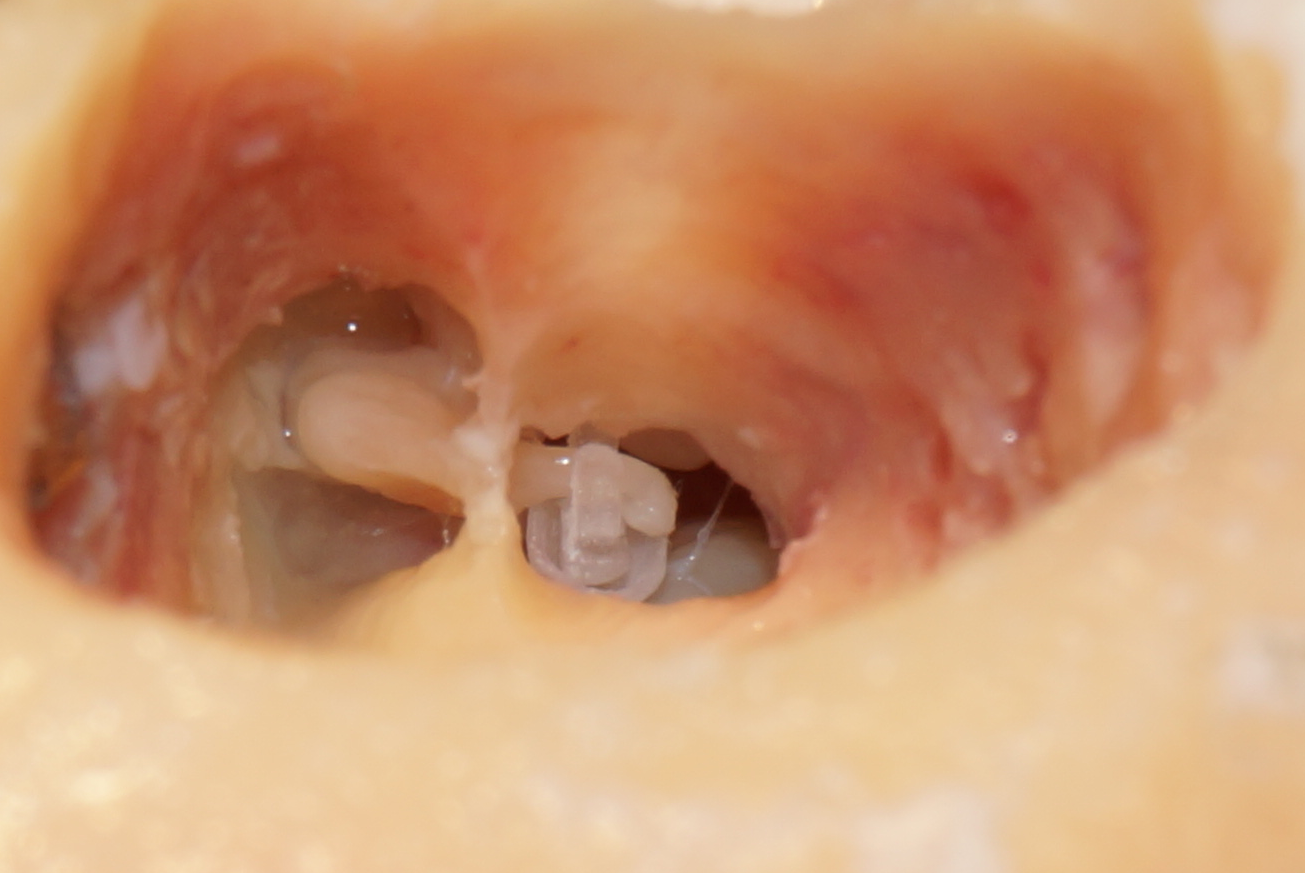

Prototyp komorowej protezki strzemiączka zaimplantowany w uchu środkowym (preparat kości skroniowej post mortem)

Nowa protezka komorowa (Zdjęcie 1) jest o wiele bardziej skuteczna oraz znacznie bezpieczniejsza dla pacjenta w porównaniu ze wszystkimi protezkami obecnie dostępnymi na rynku i stosowanymi w praktyce klinicznej. Oryginalne, opatentowane rozwiązanie konstrukcyjne działa podobnie jak struktury ucha zdrowego i nie wymaga wprowadzania elementu drgającego do ucha wewnętrznego. Protezka komorowa przywraca słuch do poziomu fizjologicznego w całym zakresie częstotliwości akustycznych (od 20Hz do 10kHz) i chroni ucho wewnętrzne przed uszkodzeniami.